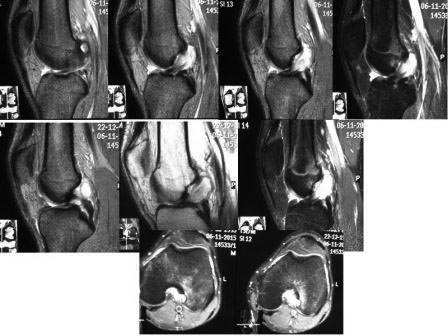

Здравствуйте, коллеги! Прошу совет по менискам и ПКС. Пациент 23 лет,

рост 170, вес 65 кг, любитель фитнеса. Дважды обращался с жалобами на

боль в коленном суставе, а так же вынужденную хромоту только после

начала бега или интенсивной ходьбы.

Подобное состояние лишало его возможности дальше заниматься спортом. Со

слов - значительной запоминающейся травмы не было, однако отметил дважды

начало этих симптомов на фоне полного здоровья после глубокого

приседания. При осмотре (10 дней от появления жалоб): ограничение

полного разгибания сустава (175 гр). Выпота, нестабильности по связкам

не выявил; сгибание в коленном суставе полное (симметрично). Помимо

ограничения разгибания слабо положительна болезненность в проекции

медиальной суставной щели. Мой предварительный диагноз по анамнезу и

клинике - "разрыв медиального мениска, п/тр блокада". Через неделю

повторно обратился уже без каких-либо жалоб, но принес МРТ, где ничего

связанного с менисками я не нашел (1,5 Тл). Смутило изображение ПКС,

описанное как "мукоидное утолщение ПКС формированием кисты". Вспомнил,

что за год вижу такую картинку третий раз и всегда у активных лиц до 28

лет, с похожей симптоматикой. Не смог найти артроскопические изображения

в книжках и инфо о последствиях такой деформации. Поделитесь опытом и

мнением по данному вопросу. Заранее

благодарен.